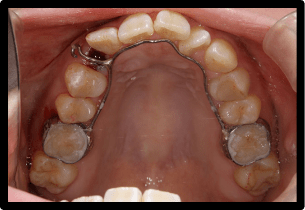

当院では以下のような装置に対応しています

固定式の装置

取り外しのできない固定式の装置となります。混合歯列期(乳歯と永久歯が混在している時期)に使用する事が多く、歯列の幅を広げることによって歯が生えるスペースを確保していきます。

BクワドヘリックスR

バイヘリックス

リンガルアーチ